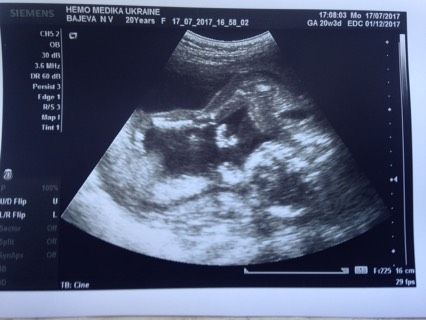

Были сегодня на УЗИ- у нас будет девочка????Слава Богу все хорошо-развивается правильно?очень толкается, даже узистка сказала шо чувствует датчиком??а еще в нашей принцессы длинные ножки -будет моделью у нас?♂️?♂️?♂️???моему счастью нет предела, я очень рада что ей в животике хорошо??она там так крутится себе) очень активная ?а еще в конце узи она показала нам ?губки бантиком ???Муж больше хотел мальчика, но после узи ходил рад как слоник????Теперь мы две недели отдыхаем а потом ложимся планово в эндокринологию ??хотя я больницы не люблю-но в это отделение я ложусь с удовольствием??⚕️???наверняка для диабетика это второй дом?Всем хорошего вечера и легкой беременности?❤?

Смогла разглядеть ваще счастье, хорошей беременности вам)

Как мило ? правда я ничего не поняла на фотке но все равно рада за вас )))